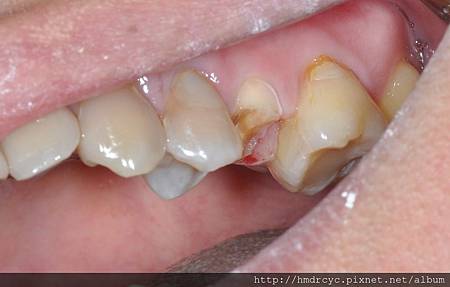

先製作鑄心將牙齒的結構增強

裝上後仍舊需要跟做假牙的步驟一樣

做好修磨與高度調整

裝上鑄心後假牙恢復就簡單了

鼓山的O先生有相同問題

因為蛀牙造成牙齒缺損嚴重

鼓山的O先生原本已經做了植牙的打算

但高雄欣美牙醫將這顆牙齒救回來

省了不少時間與預算